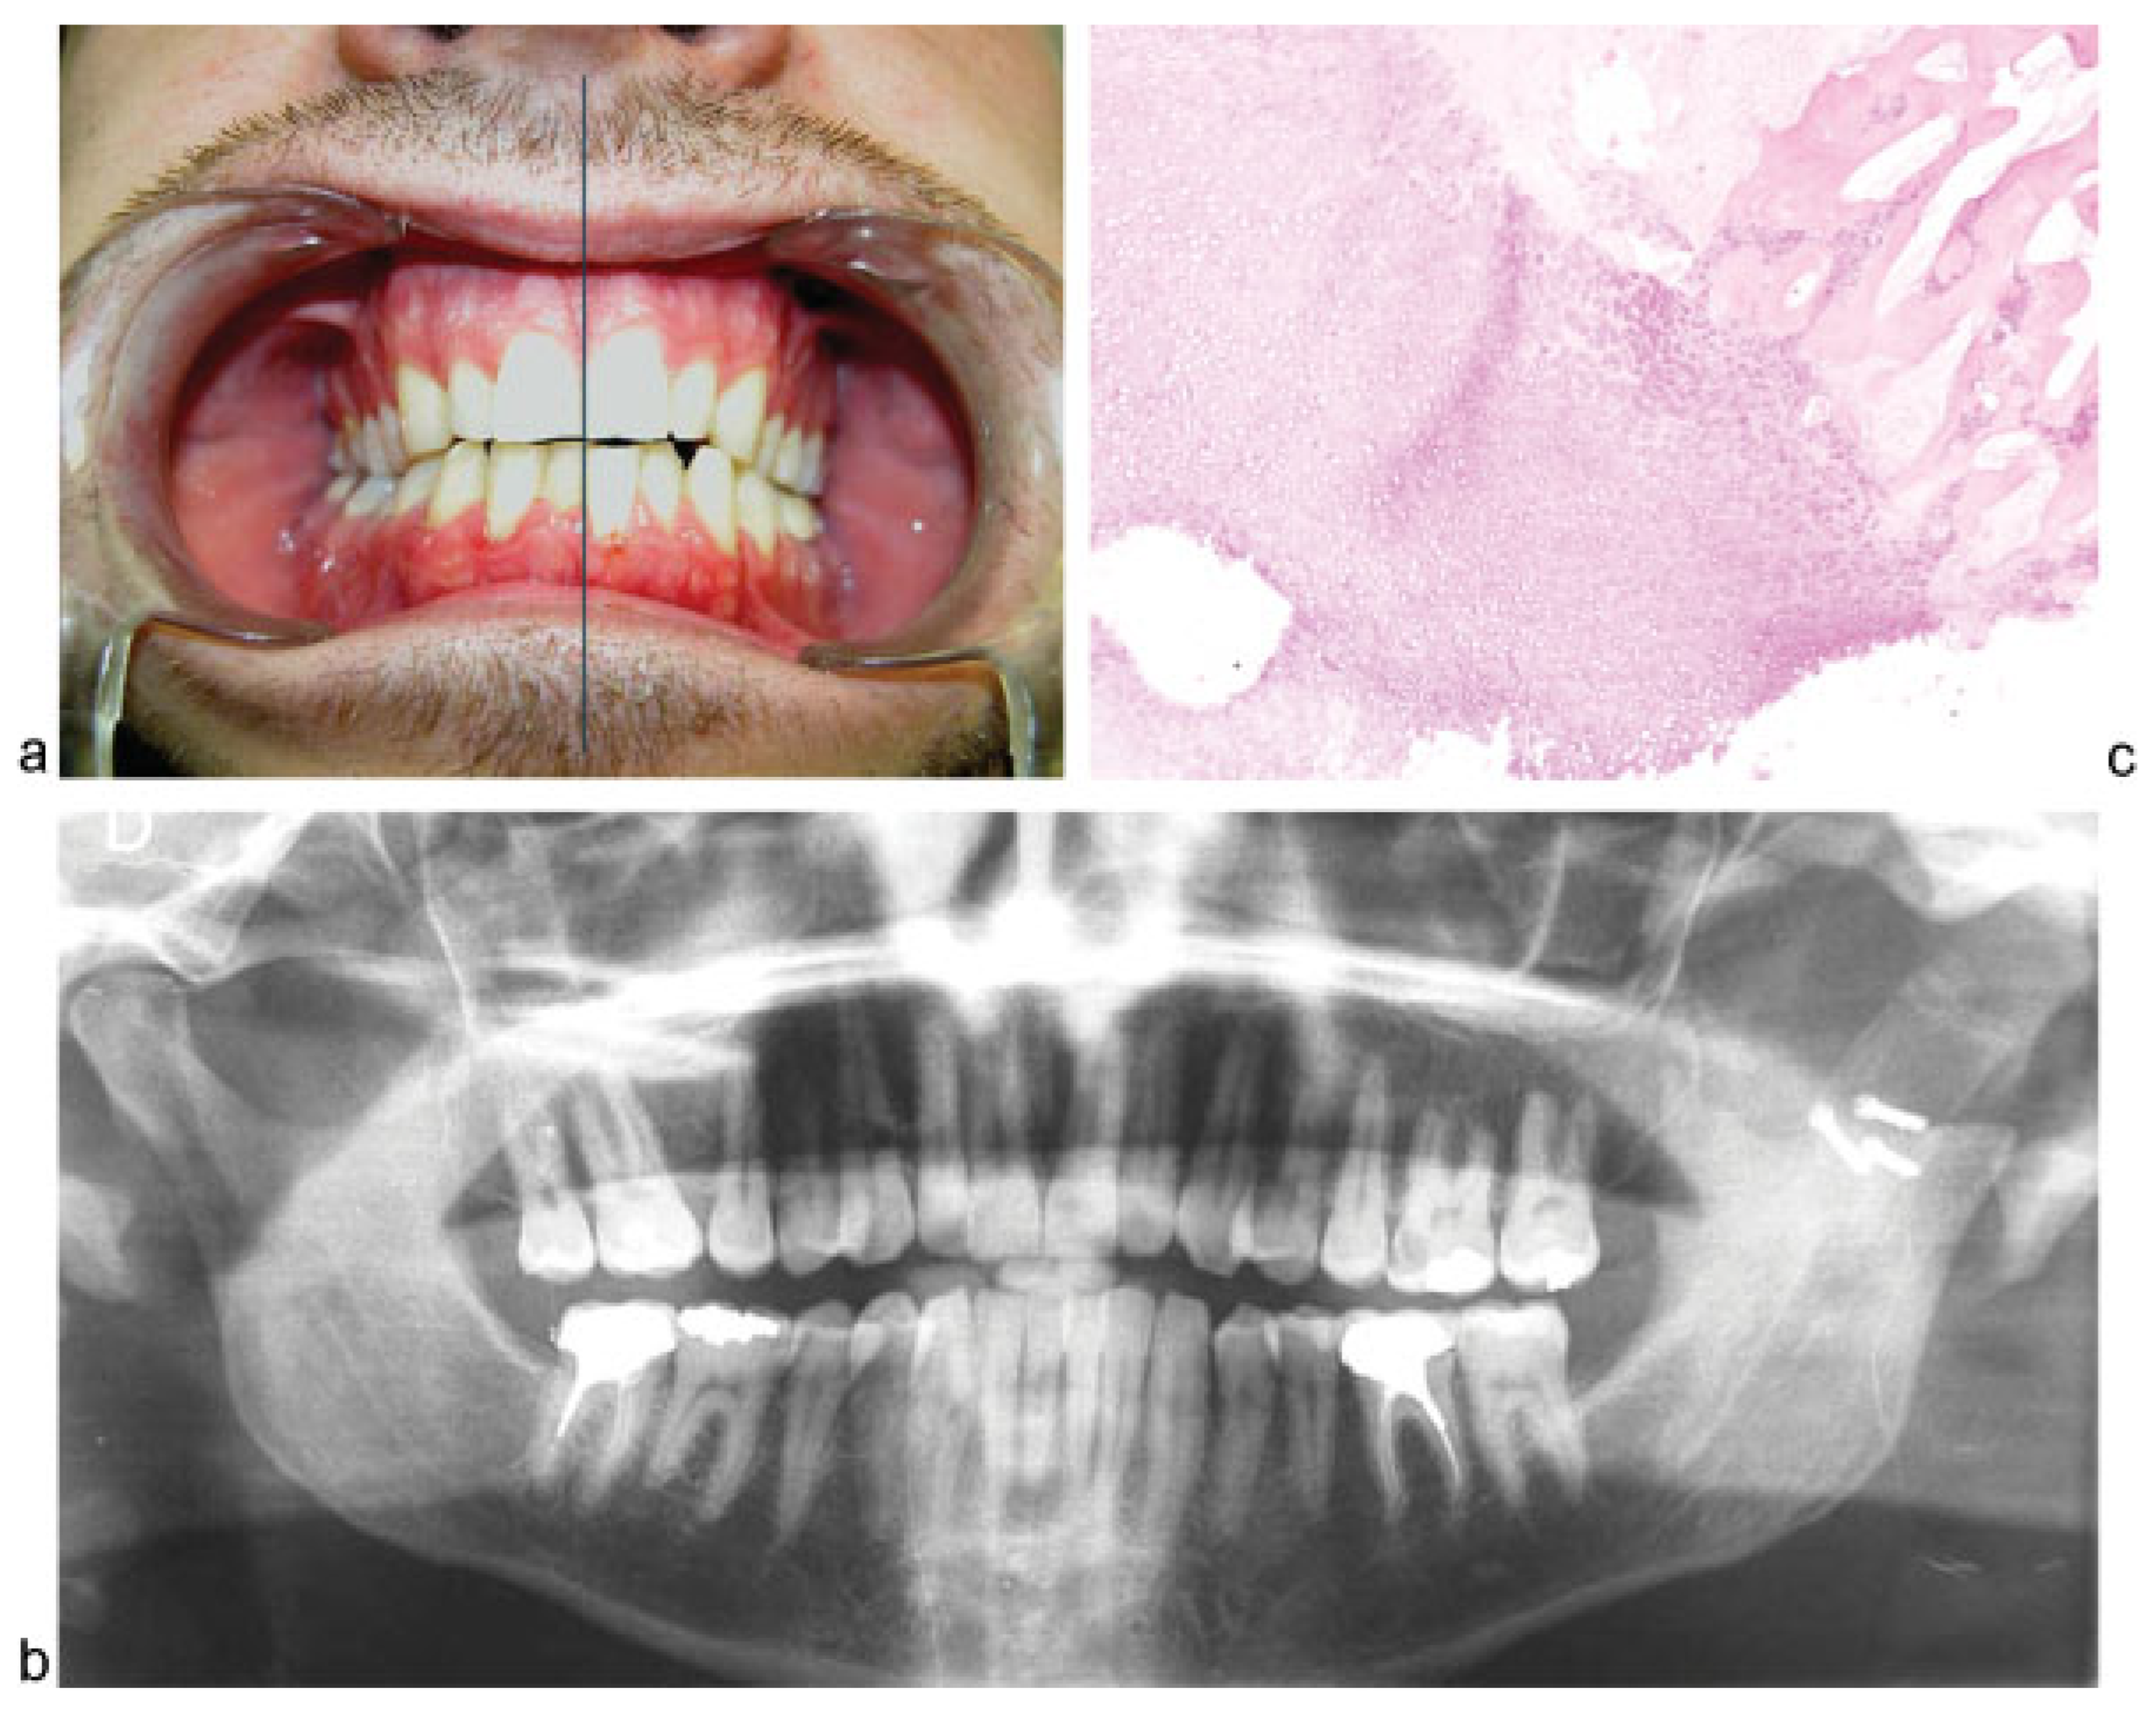

Condylar Osteochondroma Treated with Total Condylectomy and Preservation of the Articular Disc: A Case Report

Case Report